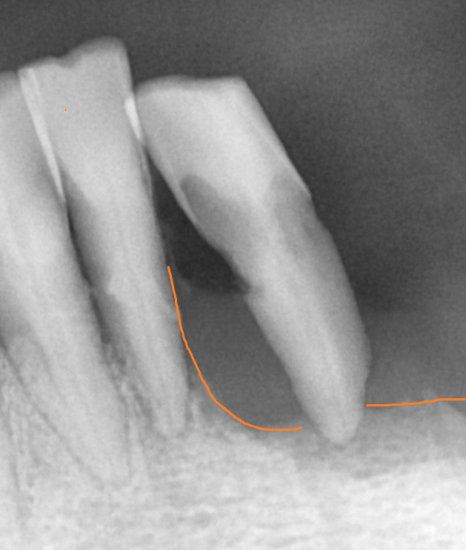

작은 x ray도 찍어보고

ct도 찍어 찍어 최대한 남길 수 있는 치아들은 남기고 싶었으나

아래 치아의 경우 몹시도 흔들리고 충치가 심하여

남아있는 치아 전부 제거가 필요했습니다.